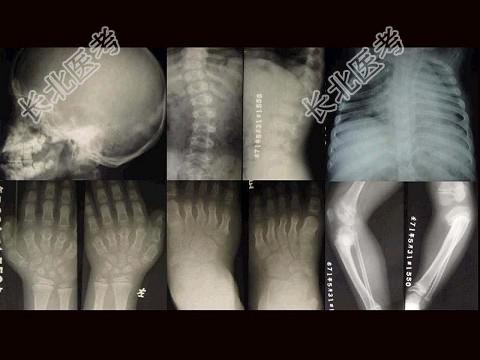

- 单项选择题女,3岁, 身体发育异常,如图所示, 最可能的诊断为 ( )

A、成骨不全

B、粘多糖病

C、软骨发育不全

D、佝偻病

E、侏儒症